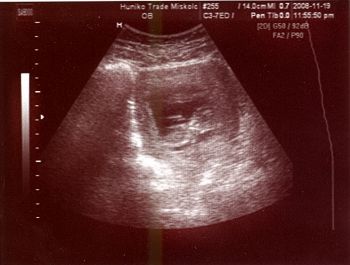

kb így nézünk ki most: